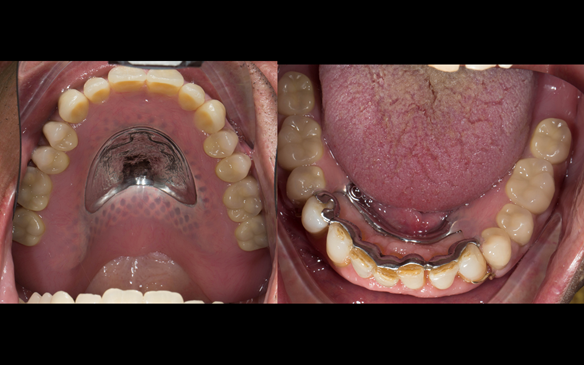

This newsletter describes in step by step detail the transition from acrylic based immediate dentures to metal based definitive dentures.

- Definitive dentures (Mk 2) – complete upper metal reinforced and lower cobalt chromium based partial of hygienic Scandinavian design to be made 9 - 12 months after extractions of all upper teeth and LR5 and LL4

The clinical situation and treatment process is shown in detail below with photographs.